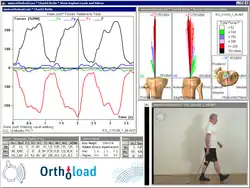

Belastung von Endoprothesen

Über die tatsächlichen mechanischen Belastungen von Endoprothesen war bisher nur wenig bekannt. Genaue Kenntnisse über die Größe und Richtung der einwirkenden Kräfte und Momente sind aber eine Voraussetzung für die Verbesserung der Implantate und deren Verankerung im Knochen. Ein Forscherteam des Julius-Wolff-Instituts der Charité – Universitätsmedizin Berlin entwickelt seit vielen Jahren Endoprothesen mit integrierter Messelektronik,[11] mit denen die Gelenkbelastung im Patienten gemessen und drahtlos an einen Computer übertragen wird. Die Belastungen, die ein Mehrfaches des Körpergewichts betragen können, werden für die verschiedenen Alltagsaktivitäten gemessen, in einer Datenbank gespeichert und im Internet Interessierten zugänglich gemacht. Neben Hüft-, Schulter- und Knieendoprothesen wurden auch Wirbelsäulenimplantate für In-vivo-Messungen instrumentiert. Auch werten die Charité-Forscher aus, wie verschiedene Metalle aus Endoprothesen freigesetzt werden und sich im umliegenden Knochengewebe anreichern. Die Forschung ergab, dass sowohl partikuläre als auch gelöste Metalle, die aus Endoprothesen stammen, im umliegenden Knochen und im Knochenmark in überphysiologischen Konzentrationen vorhanden sind. Die kollagenhaltige Schicht, die nach der Operation das Implantat verkapselt, isoliert dieses somit nicht in dem Ausmaß vom menschlichen Gewebe wie bisher angenommen.[12]

- Instrumentierte Implantate zur in vivo Messung der Kräfte und Momente Julius Wolff Institut, Charité – Universitätsmedizin Berlin

- frei zugängliche Internet-Datenbank OrthoLoad mit Ergebnissen von Belastungsmessungen verschiedener Endoprothesen (englisch)